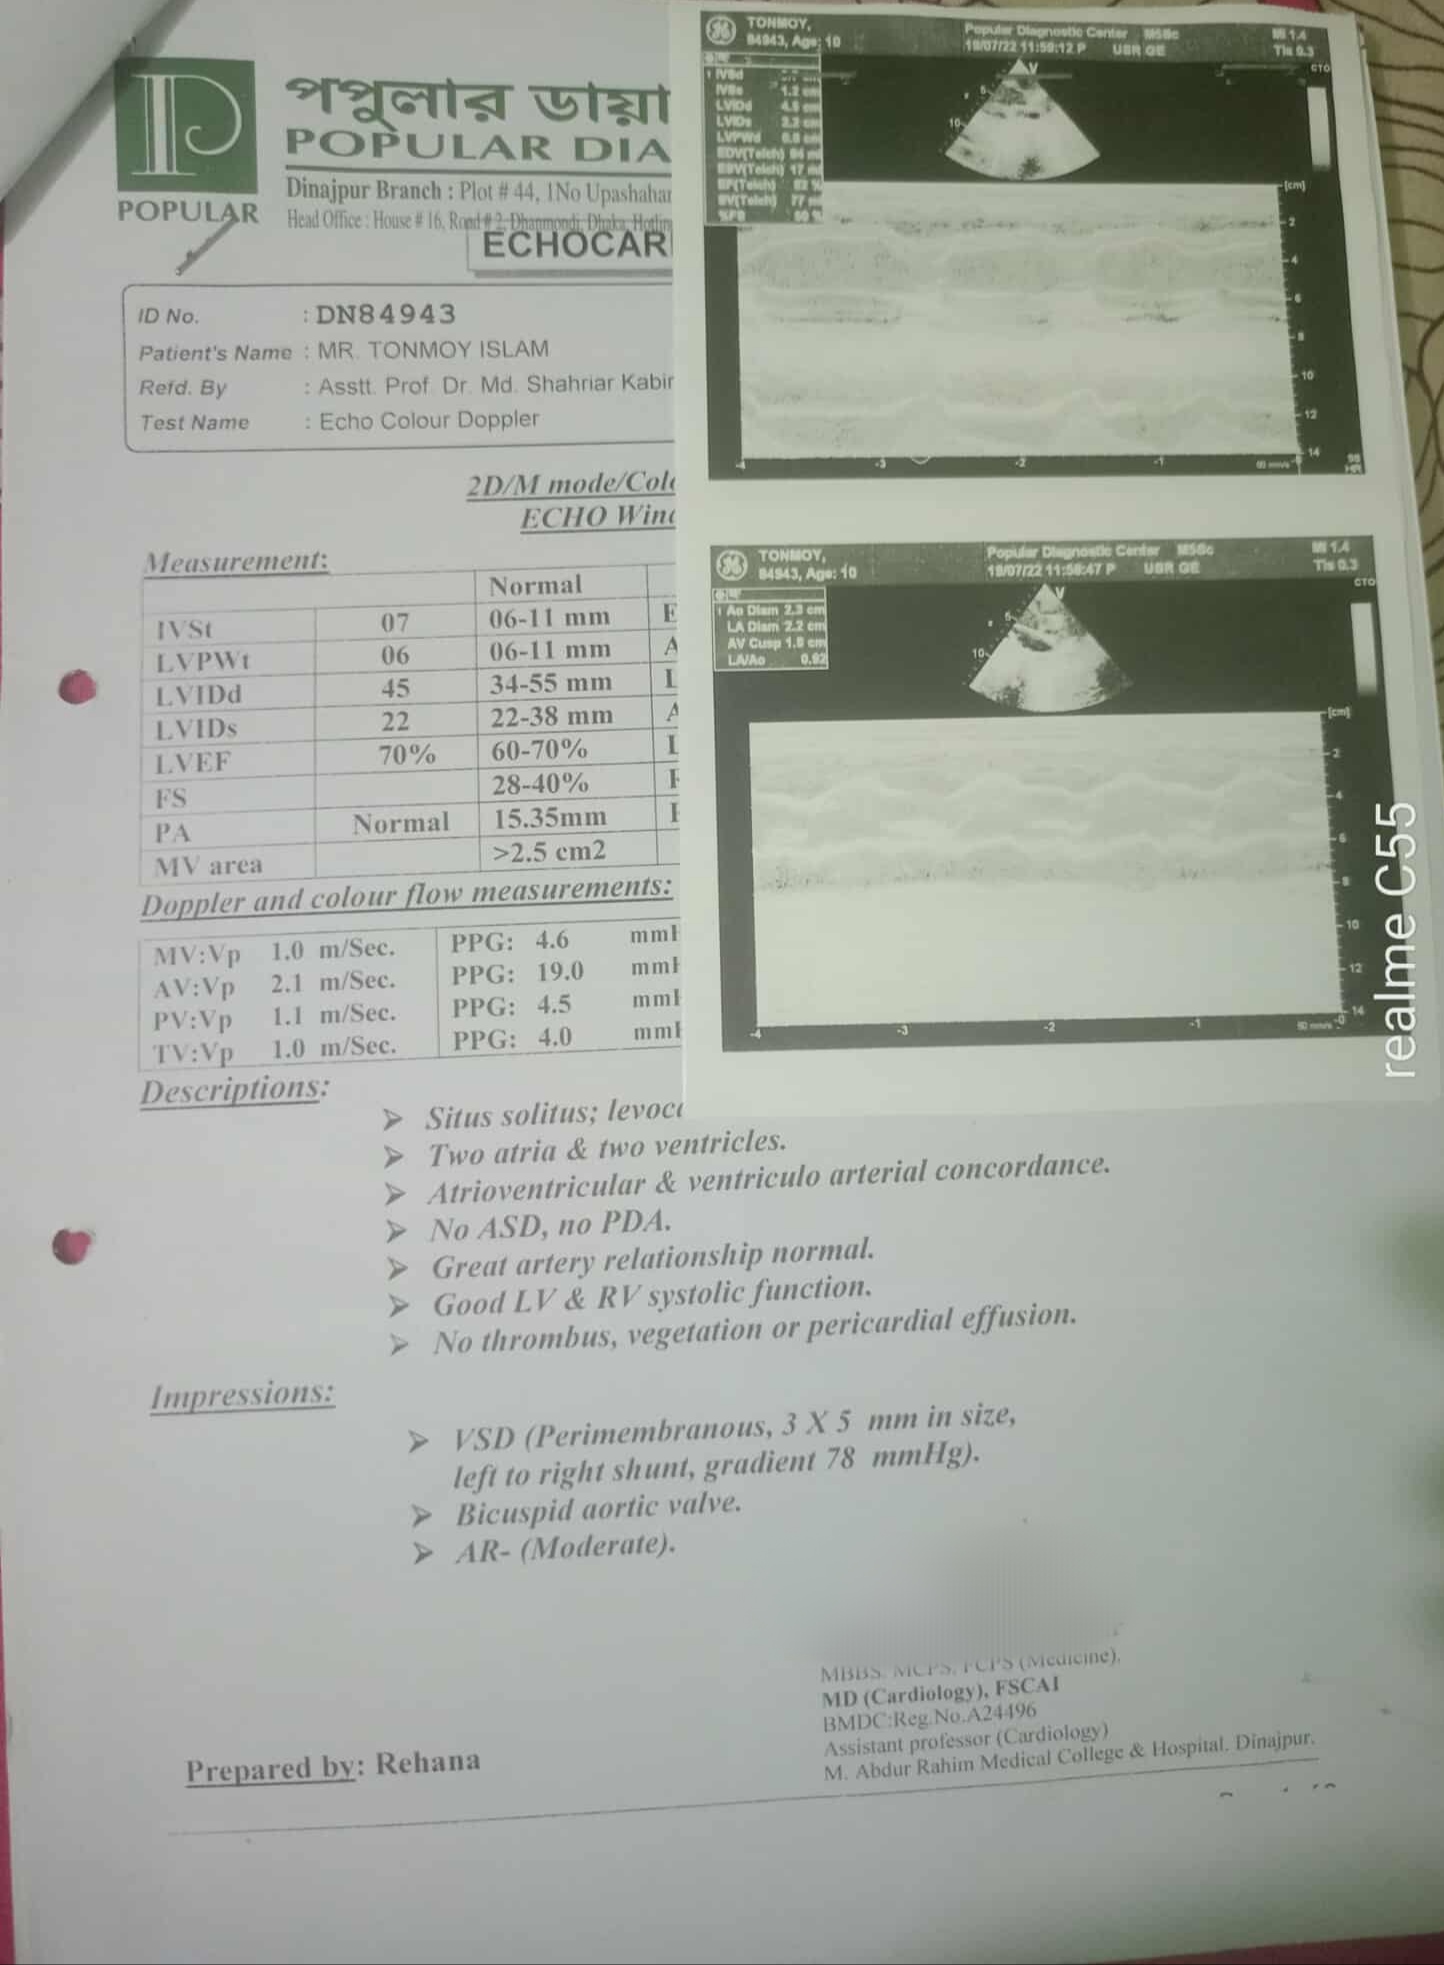

#250928A: অসহায় তন্ময় হার্টের ছিদ্র অপারেশনের জন্য সকলের কাছে সাহায্যের হাত বাড়িয়েছেন, গ্রাম: পশ্চিম গৌরি পাড়া, জেলা: দিনাজপুর।